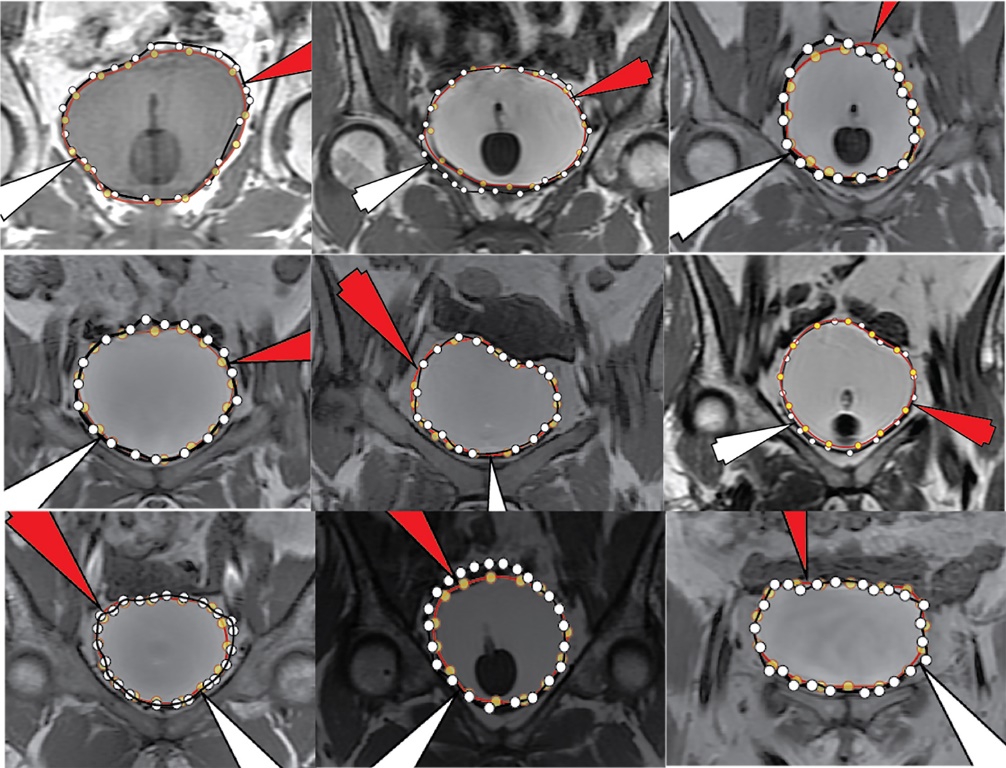

In Figure 11, we illustrate the results of the Receiver Operating Curves (ROC) for both the training and validation sets. Note that as the ROC curves shift upwards, these shapes for our ROC curves appear to indicate adequate performance across classes. The training, validation, test and overall confusion matrix are shown in Figure 12. Figure 13 illustrates all ROI data for all patients on a single figure. Figure 14 illustrates zoomed images of the ground truth and ML segmented ROIs for these patients. The red arrow is the computer-generated result, while the white arrow is the expert-generated result.Additionally, we were interested in whether the technique achieved an overall 65.2% time reduction over manual segmentation alone, as the technologist/radiologist may do some fine-tuning. However, when using the ML method, 80.0% of slices had moderate to substantially strong placement along the boundary (high levels of agreement with the radiologist delineation were in the top 37.4% of this group, without large corrections). To validate the results, we applied the Jaccard Similarity Measure, which we report to have a mean score of 0.933 (95% Confidence Interval 0.923, 0.944) with the highest possible value for complete agreement of 1.00 for that measure as shown as a distribution in Figure 15.

Figure 13Results for all 9 patients. The red arrow is the computer-generated result, while the white arrow is the expert-generated result.

Figure 14Zoomed-in regions of segmentation for all 9 patients.